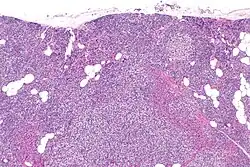

Parathyroid hyperplasia low mag.

Tertiary hyperparathyroidism is almost always related to end stage kidney disease and a secondary hyperparathyroidism.[23][4][8] Physiological changes due to the kidney damage adversely affect feedback loops that control secretion of parathyroid hormone. Renal management of phosphate is impaired in secondary hyperparathyroidism which results in hyperphosphatemia.[4][6]

Primary hyperplasia of the parathyroid gland, results from both hypocalcaemia and increased phosphate levels by decreasing expression of calcium sensing receptors and vitamin D receptors at the parathyroid gland.[8][4] These decreases in receptor expression lead to hyperfunctioning of the parathyroid. Hyperfunction of the parathyroid gland is thought to exacerbate primary hyperplasia which evolves further to a secondary more aggressive hyperplasia. Histologically, these hyperplasic glands can be either diffuse or nodular.[24] Primary hyperplasia, usually resulting in diffuse polyclonal growth is manly related to reversible secondary hyperparathyroidism. Secondary hyperplasia of the parathyroid gland is more often a nodular, monoclonal growth that sustains secondary hyperparathyroidism and is the catalyst in the progression to tertiary hyperparathyroidism. Nodular hyperplastic glands in tertiary hyperparathyroidism are distinctly larger in both absolute size and weight up to 20-40-fold increases have been reported.[25][26][24]